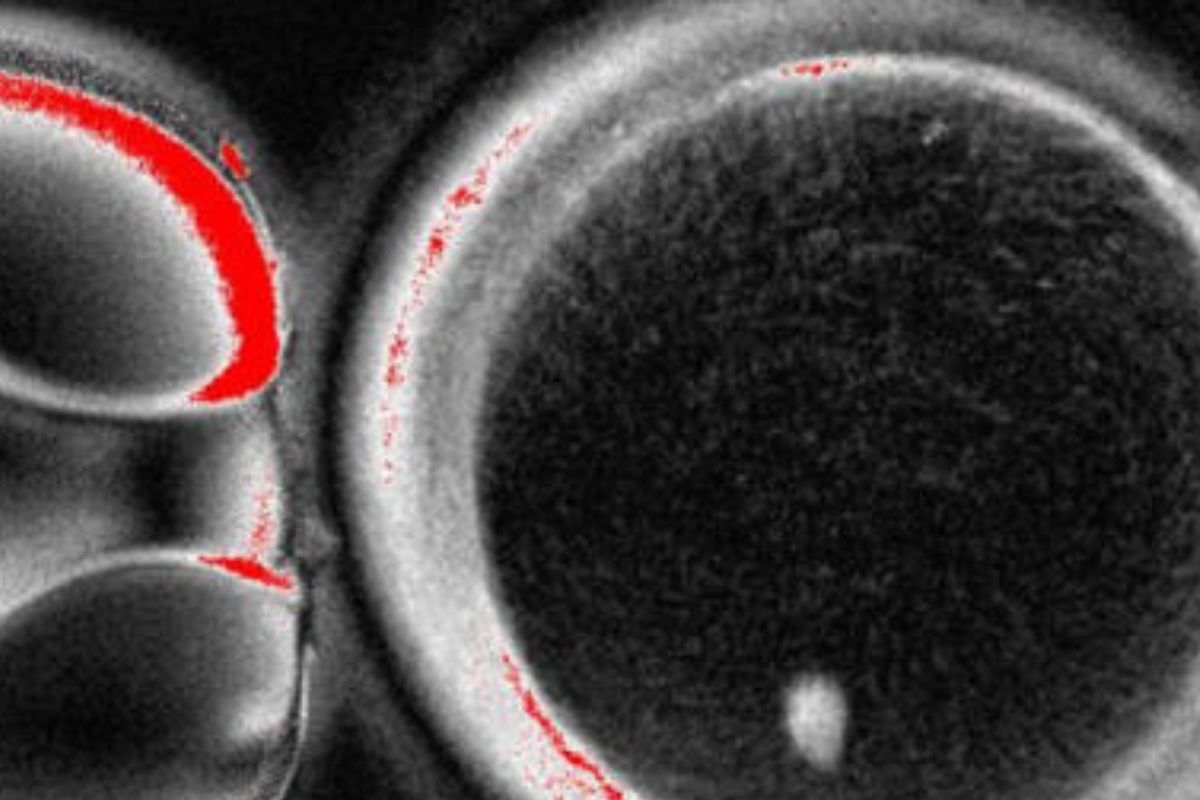

El procedimiento generó 82 ovocitos funcionales, de los cuales aproximadamente el 9% llegó a la etapa de blastocisto después de ser fecundados con espermatozoides en laboratorio. Aunque los embriones no se cultivaron más allá de este punto, el experimento sirve como prueba de concepto de que esta técnica es potencialmente factible en humanos.